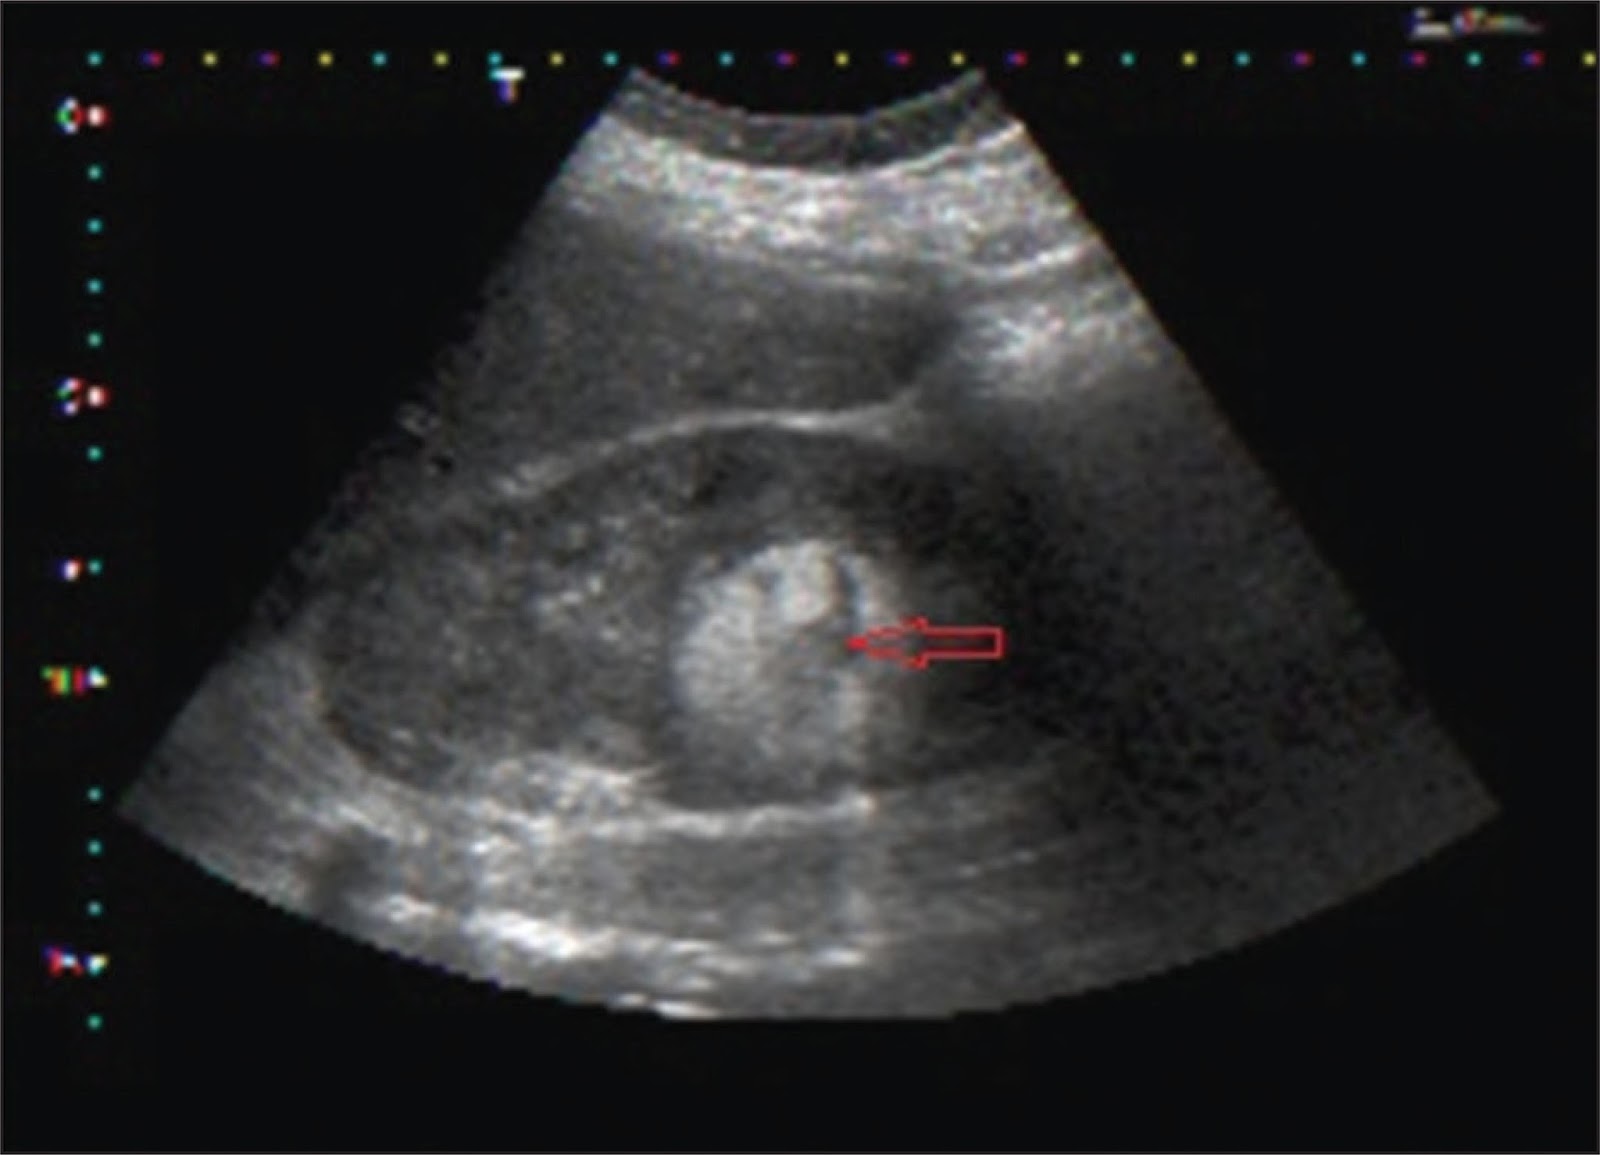

I got an econsult this morning on a young patient with an incidentally-discovered lesion on her kidney which was consistent with an angiomyolipoma. It is not uncommon to see these on ultrasound and there are a few clinical pearls that I thought I would share:

• Angiomyolipomas (AML) are benign tumors comprised of blood vessels, adipose tissue and smooth muscle. Very occasionally (more commonly in patients with tuberous sclerosis complex), they can be malignant. Malignant AMLs are more likely to be fat-poor, hypoechoic tumors (termed epitheliod AML).

• The hyperechoic nature of these lesions on ultrasound is due to fat in the tumor rather than the vascularity.